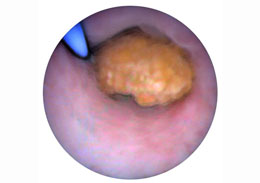

The ureteroscopy is a procedure to a test. In this examination the ureteroscopy uses a small lighted tube for ureters test. The ureters are thin tubes, it is connected to the kidneys and the bladder, these thin tubes carries urine from the kidneys to bladder. By using an ureteroscopy the specialist can look a stone in the ureter and he can remove stone with the little basket at the ending of a wire inserted by an extra channel in the ureteroscopy.